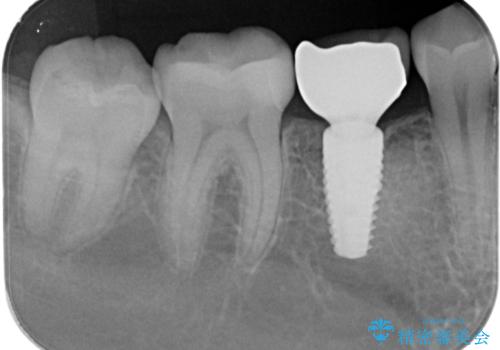

- 過去に抜けてしまった歯のところにインプラントを入れたいとの事で来院。

CTで確認したところ骨の高さや厚みがインプラント埋入できる状態でしたのでインプラント治療を行いました。

併用して銀歯も気になるとの事でしたのでセラミック治療も行いました。

- インプラント体、アバット、仮歯、ジルコニアクラウン・42.9万円 e-maxインレー・7.7万円 費用は治療当時の料金となります

適合の良いセラミックが入りました。